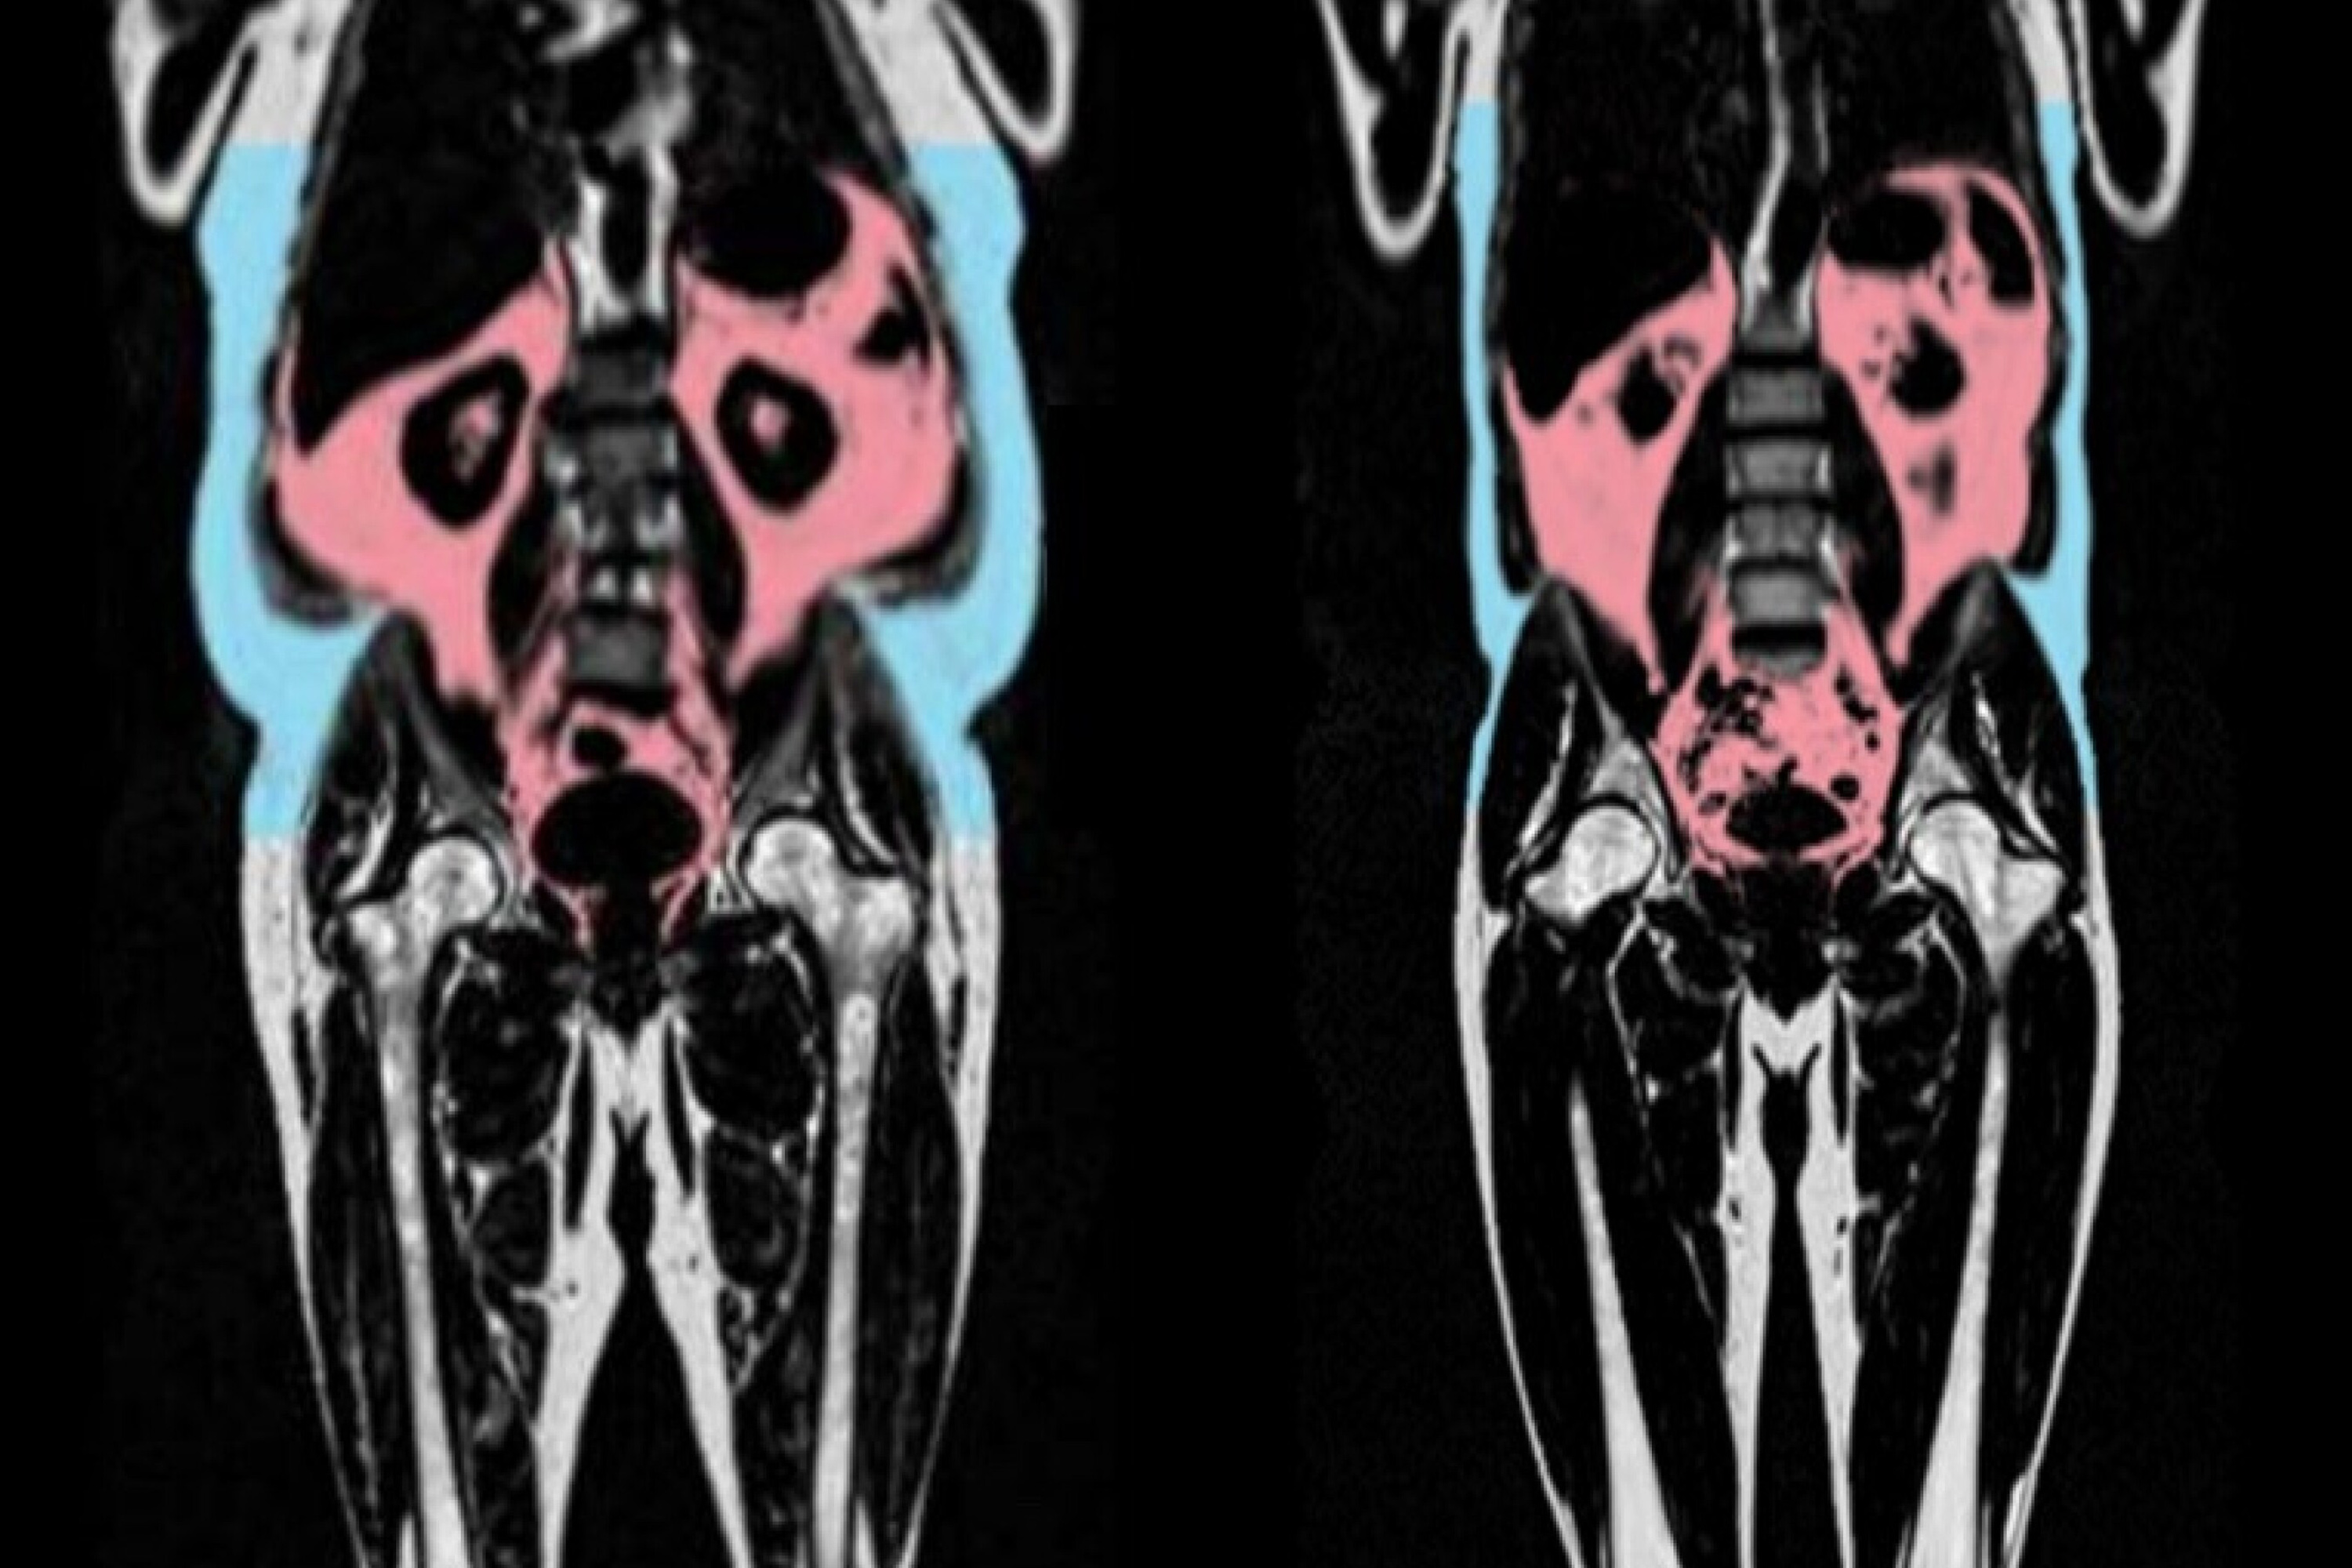

An image of an MRI Scan showing body fat

In the study, published in the European Heart Journal, the scientists analysed data from 21,241 participants in UK Biobank, which includes whole body imaging to map the amount of fat and where it is located in the body.

The UK Biobank data also includes detailed imaging of the heart and blood vessels. Artificial intelligence was used to analyse these images to capture signs of organ ageing - such as tissues becoming stiff and inflamed. An individual was given a “heart age” which can be compared to their actual age at the time of the scan.

The researchers found that faster heart ageing was linked to having more visceral adipose tissue. Visceral adipose tissue is fat found deep inside the abdomen around organs such as the stomach, intestines, and liver. This type of fat cannot be seen from the outside, and some people can have large amounts of visceral fat despite having a healthy weight.